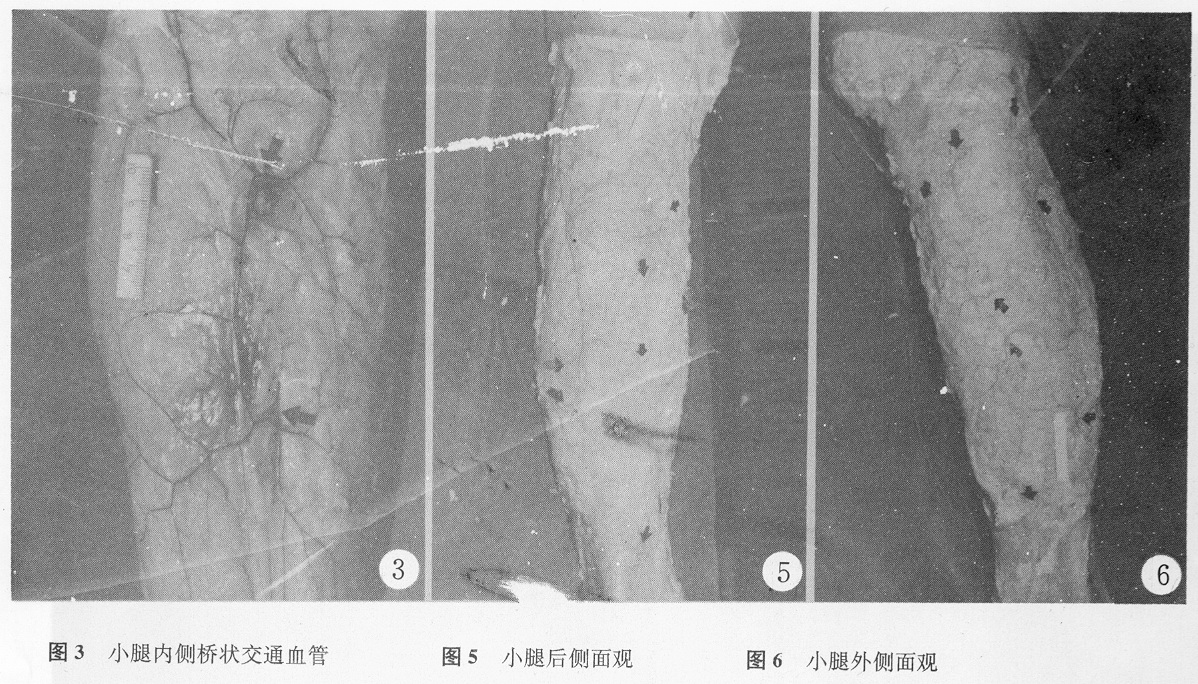

小腿后肌间隔深筋膜表面也有一类似血管丛,其中有腓肠外侧皮动脉和腓动脉干细小分支及肌皮穿支组成的桥状交通血管(外侧桥状交通血管)(图3)(表3)。交通血管汇入前常先发出分支。主干以向远端斜行为主,体表投影为股二头肌止点到跟腱外缘的连线,在小腿中、下1/3交界偏上转向前行终止于小腿后肌间隔穿出的最后一个交通血管的穿筋膜点。分支很快进入浅筋膜浅面,分布范围在血管桥两侧5cm内。最远端一交通支的位置较恒定,口径在0.6?.0之间(图3)。

T检验处理后得,内上、下和后上3区之间相比较,轴向性指数差别不显著。后下、外上、外下3区间的轴向性指数相差也不显著。但不论前述3区中的哪一区与后述3区中的任何一区比较轴向性指数都有显著差别。前3区的轴向性指数明显高于后3区。说明前3区内的皮动脉分布范围多呈长条状,而后3区者多呈接近于圆形或不规则形的分布(图5)。分布范围呈长条状的血管其分布范围的长轴与小腿长轴平行或接近平行。